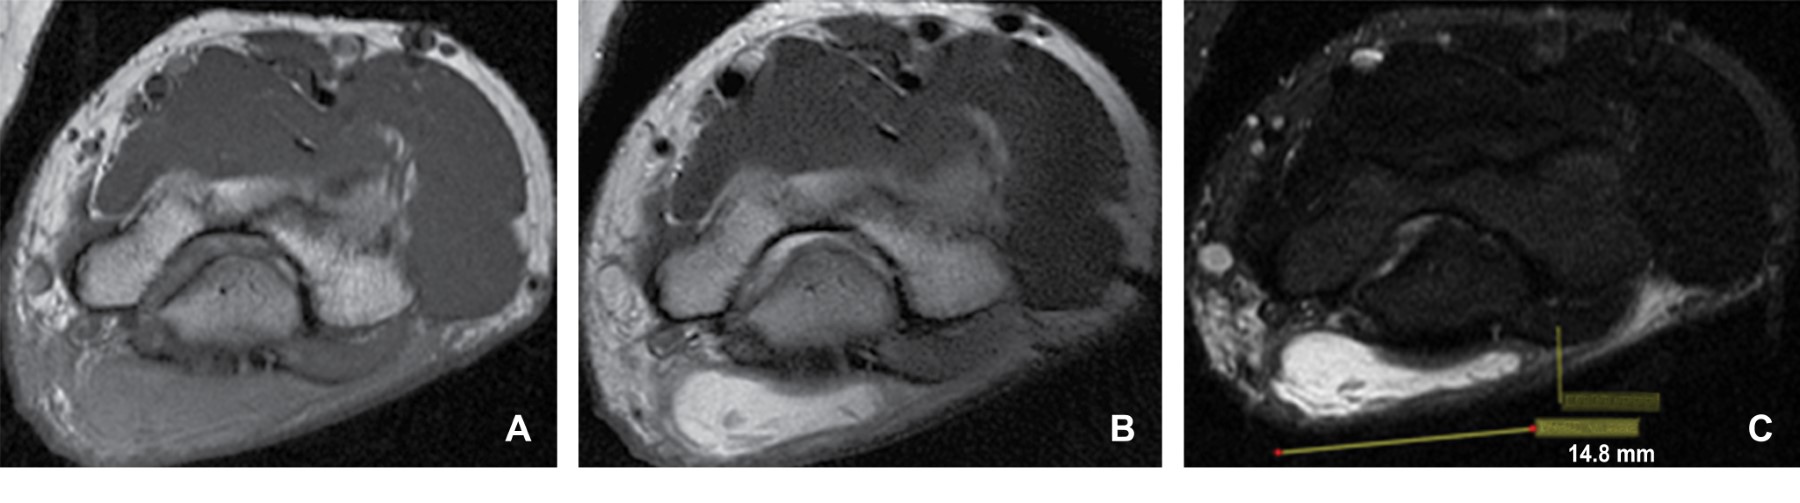

Masculino de 40 años de edad que refiere aparición de zona de enrojecimiento y pequeño abultamiento a nivel del codo izquierdo de tres semanas de evolución, inicialmente adjudicada a piquete de insecto. Acude a médico particular que le administra tratamiento antibiótico sin mejoría, por lo que acude a una segunda evaluación médica donde a la exploración física se evidencia un notable aumento de volumen en región olecraneana, de consistencia blanda con eritema, razón por la que su médico decide investigar a fondo y solicita estudios de laboratorio, los cuales revelaron una elevación de los niveles séricos de ácido úrico y se diagnosticó con gota, por tal motivo se solicita resonancia magnética de codo izquierdo. En el estudio de resonancia magnética simple se identifica una imagen sacular a nivel del olecranon, bien delimitada, heterogénea en su interior, de comportamiento isointenso heterogéneo en el T1, hiperintenso heterogéneo en el T2 e hiperintenso heterogéneo en el T2 con saturación grasa. Dicha imagen midió 39.8 × 14.8 mm en el plano axial, 18 × 46.5 mm en el plano sagital y 40.21 × 46.07 mm en el plano coronal (Figuras 1, 2 y 3), con una pared que midió 2.42 mm de grosor (Figura 2); localizada a nivel de las bursas del olécranon en específico a nivel de la bursa olecraneana superficial.

Figura 1